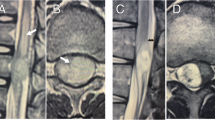

Systematic search yielded 20 publications dealing with AXM for IMSCT. In summary, 4 tumor entities were analyzed in 23 experiments using ~337 animals, mainly investigating glioblastoma or gliosarcoma biology. Studies varied regarding the use of engrafted animals, surgical techniques and tumor burden. Most commonly authors used heterotopic, transdural injection of immortalized brain tumor cell lines (1 × 105 in 5 µl) into the thoracic spinal cord of immunocompromised rats. Quality assessment demonstrated an unclear risk of bias in most cases.

Caplan J, Pradilla G, Hdeib A, Tyler BM, Legnani FG, Bagley CA. A novel model of intramedullary spinal cord tumors in rats: functional progression and histopathological characterization. Neurosurgery. 2006;59:193–200.

Mavinkurve G, Pradilla G, Legnani FG, Tyler BM, Bagley CA, Brem H, et al. A novel intramedullary spinal cord tumor model: functional, radiological, and histopathological characterization. J Neurosurg Spine. 2005;3:142–8.